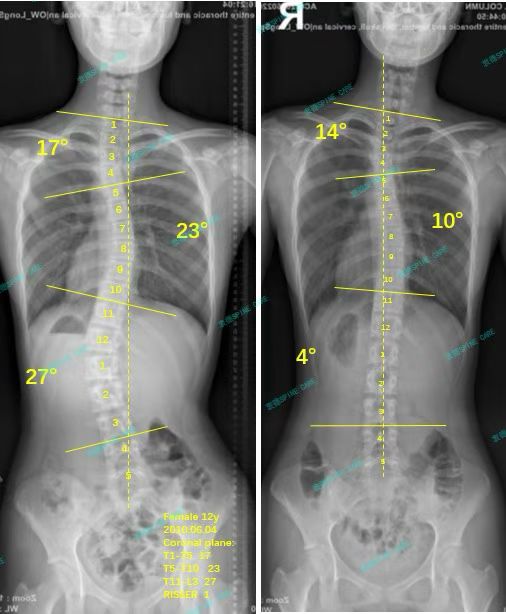

直到现在,我已经在这里训练了3年多了,杨医生非常负责,时刻关注我的体态,也会及时给我调整训练计划,康复师小姐姐都很耐心,经常鼓励我,最近一次的拍片显示我的胸弯角度从23度降到10度,腰弯从27度降到4度,上胸弯从17度降到14度,胸椎旋转从5度降到1度,我的体态也在越来越好,现在已经非常挺拔了,但我依旧会继续坚持在这里训练,杨医生说,等我成年后,这个角度基本就不会再加重了。

Until now, I have been training here for more than 3 years. Dr. Yang is very responsible, always paying attention to my posture and adjusting my training plan in a timely manner. The rehabilitation therapists are very patient and often encourage me. The most recent X-ray showed that my thoracic curve angle decreased from 23 degrees to 10 degrees, my lumbar curve from 27 degrees to 4 degrees, my upper thoracic curve from 17 degrees to 14 degrees, and my thoracic rotation from 5 degrees to 1 degree. My posture is getting better and better, and now I am very upright. But I will still continue to train here. Dr. Yang said that once I reach adulthood, the angle will basically not get worse.